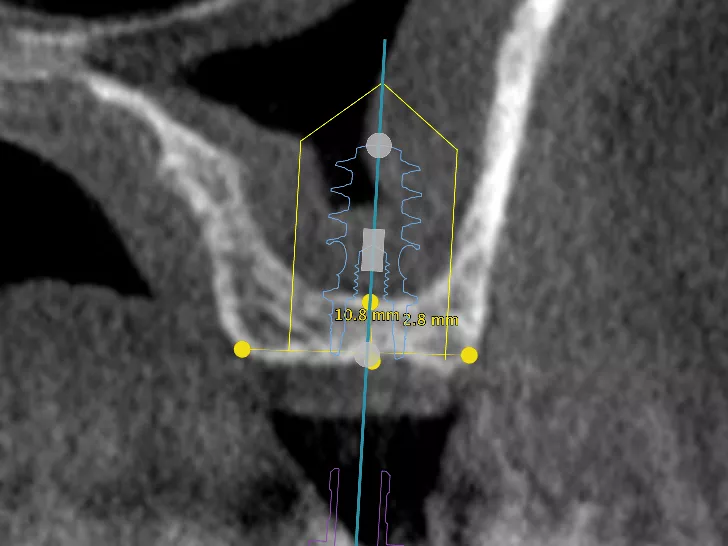

Upon examination, it was found that the patient had a broad crest and thick periodontal tissue with satisfactory gingival height. A cone beam examination confirmed that the width of the bone crest was 10.8 mm. However, the residual bone height was only 2.8mm, which was deemed insufficient for the planned implant (Axiom® BL X3 Ø 4mm, length 10mm) without hard tissue augmentation. Nonetheless, implant placement with a concomitant sinus lift can be considered when bone heights are ≥ 2 mm ​[1-4]​. As a result, a surgical decision was made to place an Axiom X3® Bone Level implant to replace 16, along with a simultaneous sinus lift to facilitate both implant placement and bone regeneration in one procedure.​

2a. 2b. Pre-operative CBCT scan :

Crestal bone dimensions width 10.8 mm and height: 2.8 mm.

The Alpha angle, formed by the anterior lateral wall of the maxillary sinus and the palatal wall, is favorable at > 60° ​[1]​.

The thickness of the sinus mucosa is favorable > 1.5 mm, indicating a limited risk of perforation. Thickening is not pathological in this patient.

The thickness of the vestibular bone wall is normal, between 1 and 2.5 mm. No intra-sinus septum.

The Beta angle, formed by the palatal wall of the maxillary sinus and the inter-sinus-nasal septum, is on the other hand very closed, which may entail risks in the detachment of the mucosa in this area.